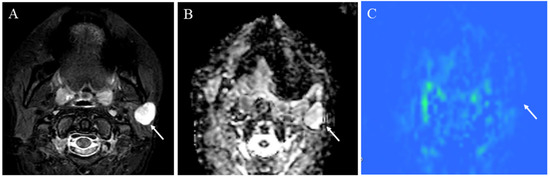

5.1.2. Hypervascular Lesions

5.1.4. Other Head and Neck Tumors

- Tanaka, F.; Umino, M.; Maeda, M.; Nakayama, R.; Inoue, K.; Kogue, R.; Obara, M.; Sakuma, H. Tumor blood flow and apparent diffusion coefficient histogram analysis for differentiating malignant salivary tumors from pleomorphic adenomas and Warthin’s tumors. Sci. Rep. 2022, 12, 5947. [Google Scholar] [CrossRef]